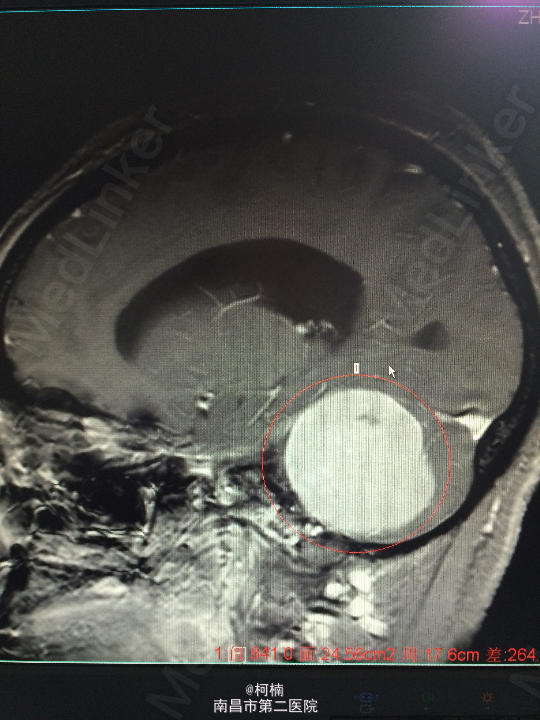

主诉:反复头晕、头痛伴呕吐及行走不稳10月余 病史:患者老年女性,55岁,10余月前开始出现头晕、头痛伴呕吐及行走不稳,无肢体乏力、肢体抽搐、意识障碍等不适,于当地医院诊治行头颅MR提示:右侧小脑角占位,考虑肿瘤。 查体:神经系统体查未见明显异常

查体:神经系统体查未见明显异常 辅助检查:头颅MR提示右侧桥小脑区占位性病变,考虑脑膜瘤。四脑室狭窄,变形,幕上脑室积水,小脑扁桃体疝

诊断:右侧小脑脑膜瘤 处理:先行介入栓塞肿瘤供血动脉,再行开颅手术治疗,术后予组织病理检查,提示:脑膜瘤